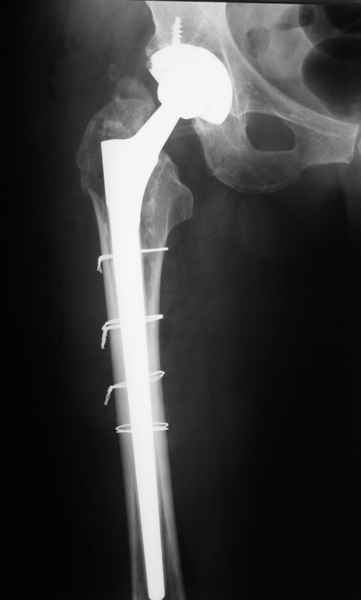

2. Применение ножки дистальной фиксации, мы отдаем предпочтение ножке Вагнера с фиксацией проксимального отдела на ножке. Более травматичное вмешательство, но при стабильной фиксации ножки реабилитация идет в обычном режиме.

Хочется показать два подобных случая, П-ка З. 72 лет и п-т Г. 80 лет. Сразу принимаю замечание, что это были ножки цементной фиксации, просто под руками не было бесцементника.

Пациента удалось осмотреть недавно. Достигнутый результат сохраняется. Перелом бедра сросся. Конечность опорная и безболезненная, ходит без трости. Ножка, похоже, реинтегрировалась, как и надеялись. Снимки и фото в приложении. Комментарии приветствуются.

Надо ли что-то делать дальше, как полагаете? Убрать винты? Убрать "удлинитель ножки"? Или оставить все, как есть? Спасибо заранее.